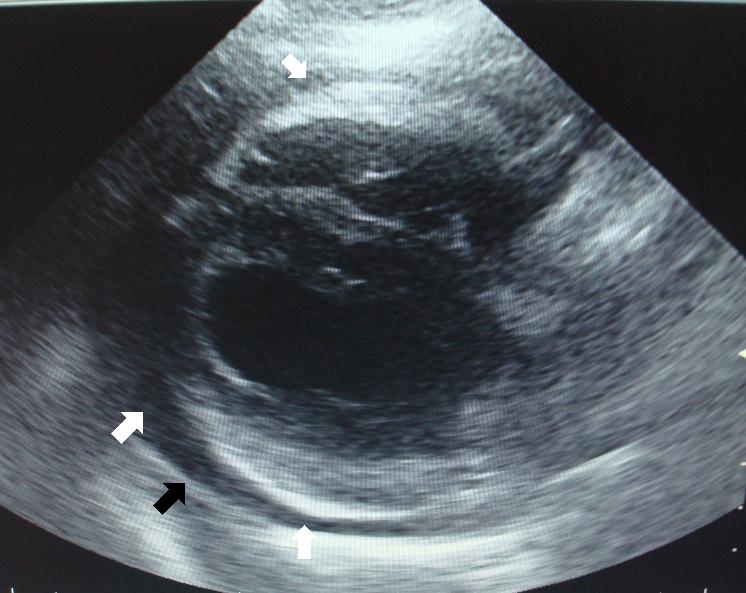

Jako další se provedlo ultrasonografické vyšetření dutiny břišní, které nám potvrdilo přítomnost volné tekutiny (bílá šipka) a abnormální zvětšení jater se zaoblenými okraji jaterních laloků (černá šipka). V jaterním parenchymu byly rovněž identifikovány rozšířené větve systémového žilního krevního oběhu.

Hemoperikard-SONO břicha-peritoneální efuze1